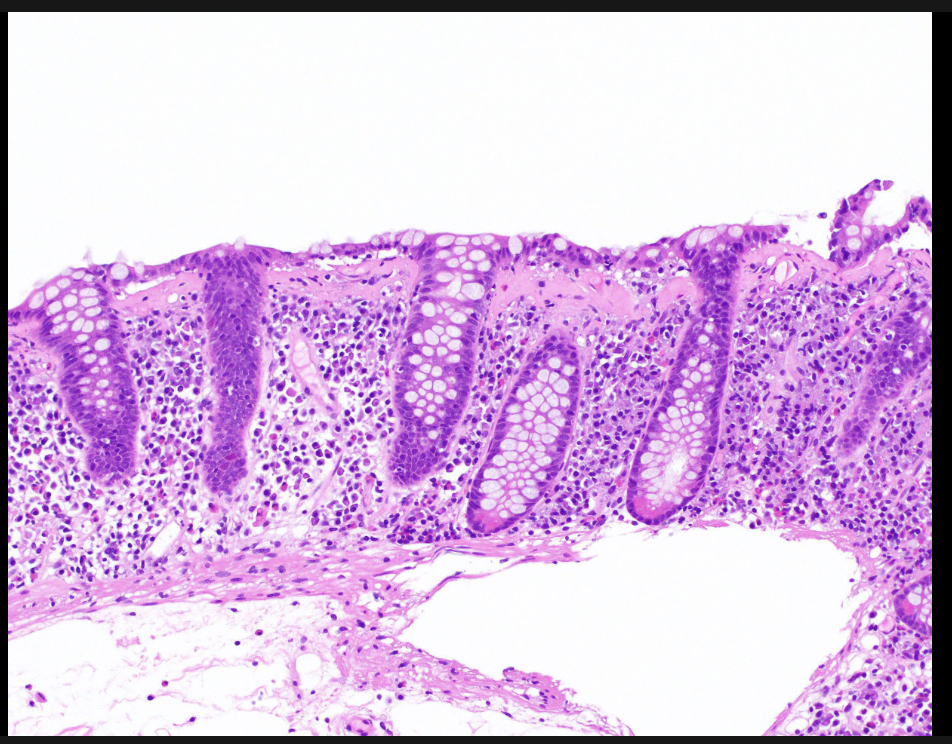

Patient with diarrhea

A

lymphocytic colitis

1st line therapy- budesonide 9mg/day for 8 weeks, then 6mg for 2 weeks, then 3mg for 2 weeks

for recurrence give 6mg taper over 6 months